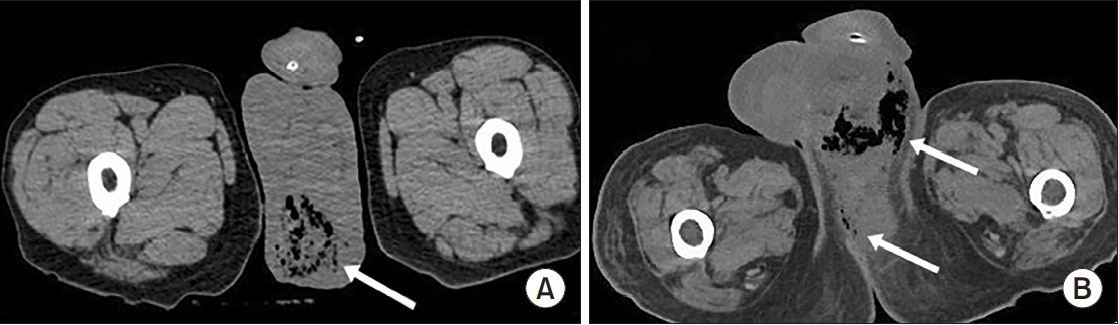

A total of 84 patients were included in this study. The mean age was 58.1±15.9 years, and 95.2% were male. The most common comorbidity was diabetes mellitus (42.9%), followed by hypertension (36.9%). Sepsis occurred in 38.1%, ICU care was required in 42.9%. Among patients who required ICU care, the mean ICU stay was 8.0 days. The overall in-hospital mortality rate was 14.3% (Table 1). The most frequent organisms from abscess cultures were E. coli (29.8%) and K. pneumoniae (19.0%), with Staphylococcus spp. and other organisms comprising 10.7% and 33.3%, respectively (Supplementary Fig. 1). Representative CT images from 2 illustrative cases are shown in Fig. 1.